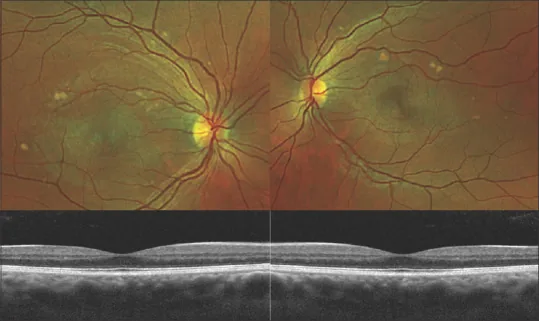

両眼対称性・多発性の黄白色網膜下病変が主たる眼底所見である。病変の形態は多様であり、円形・楕円形・曲線状など様々な形態をとる。主に黄斑部に位置するが、血管弓沿いにも水疱状(bleb-like)病変が認められる場合がある。1)

病変内の卵黄状物質は重力に従って下方に沈殿し、半月状(meniscus-like)の液面形成(偽前房蓄膿;pseudohypopyon)を呈することがある。1)硝子体炎症や血管炎所見は認めず、視神経乳頭の異常も伴わない。1)

AEPVMの診断は除外診断であり、類似疾患を体系的に除外する過程が必要である。マルチモーダルイメージングの組み合わせが診断の要となる。1)

FAと自発蛍光検査(FAF)の反転パターンは本疾患の特徴的な所見である。

Section titled “7. 最新の研究と今後の展望(研究段階の報告)”マルチモーダルイメージングによる診断の確立

Section titled “マルチモーダルイメージングによる診断の確立”カラー眼底写真・SD-OCT・FAFの組み合わせにより、侵襲的検査なしにAEPVMの臨床診断が可能になりつつある。1)各モダリティが相補的な情報を提供し、特にFAFとFAの反転パターンが診断の鍵となる。